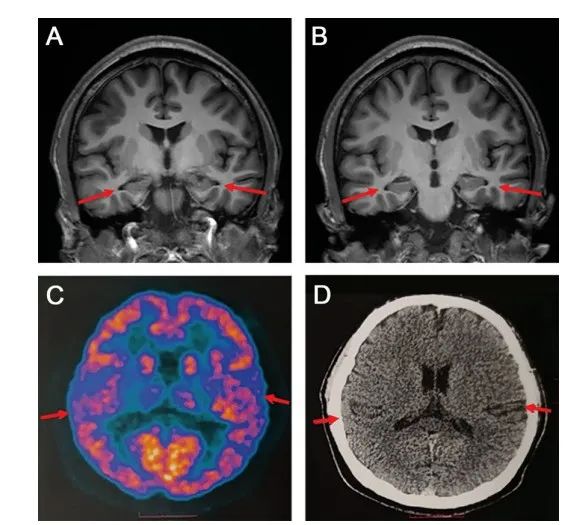

经多种检测方式发现,患者存在轻度脑萎缩,部分脑脊液指标异常,是迄今为止已被报道的符合AD诊断标准的最年轻病例。

研究发现,在老年痴呆症症状出现的前11~15年,就有认知障碍迹象发生。影像学检查还发现,症状出现前3~9年,内侧颞叶改变发生变化,而内侧颞叶与记忆相关。